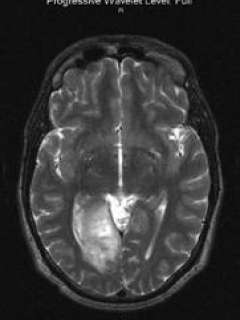

The case history of Robert

Robert is a 38 year-old right-handed man, born with congenital blindness of the left eye, who first presented with flashes of kaleidoscope-type color changes in his right eye around May 2004. His description of these symptoms were consistent with visual seizures, which are the abnormal, disorganized firing of neurons within the visual centers of the brain that may create the experience of flashes of light and/or color. Although he had had seizures in the past, these symptoms were new, so he underwent an MRI scan of his brain. MRI at the time revealed a mass in the occipital lobe, the main vision center of the brain, on the right side. After a trial of medical management with anti-seizure medications and serial MRI scans to see if the mass was actively growing, radiologic evidence of disease progression in September 2005 brought him to Ronald Reagan UCLA Medical Center in search of surgical treatment.

Preoperative functional MRI T2 axial view: